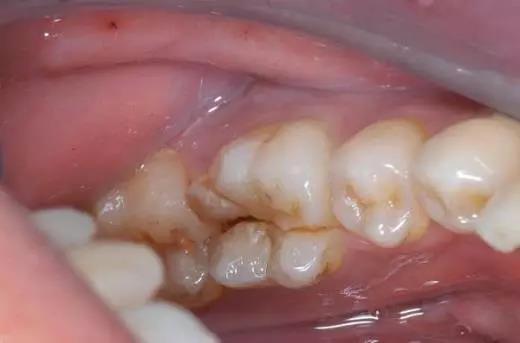

看似坚固的牙齿,其实也很脆弱。当我们咬坚果、螃蟹、骨头等硬物,牙齿的下场很可能就变成了这样

或这样

牙齿开裂,医学称牙隐裂,它是牙齿表面不正常的细小裂纹,通常不易被发现。

隐裂牙一旦形成,裂纹会越来越长,越来越深,不会自己停下来。裂纹浅的时候没有症状,进一步发展,偶尔会在吃东西的时候有一过性的酸痛感。进一步发展接近牙髓,患者咀嚼痛、冷热刺激痛,患者吃东西时有意避开患牙,不能用冷水刷牙,不敢吃过冷过热的食物,如不进行治疗,牙齿随时都可能劈裂。轻者牙冠劈裂,重者牙根劈裂,导致牙齿拔除。

(图片来源于网络)